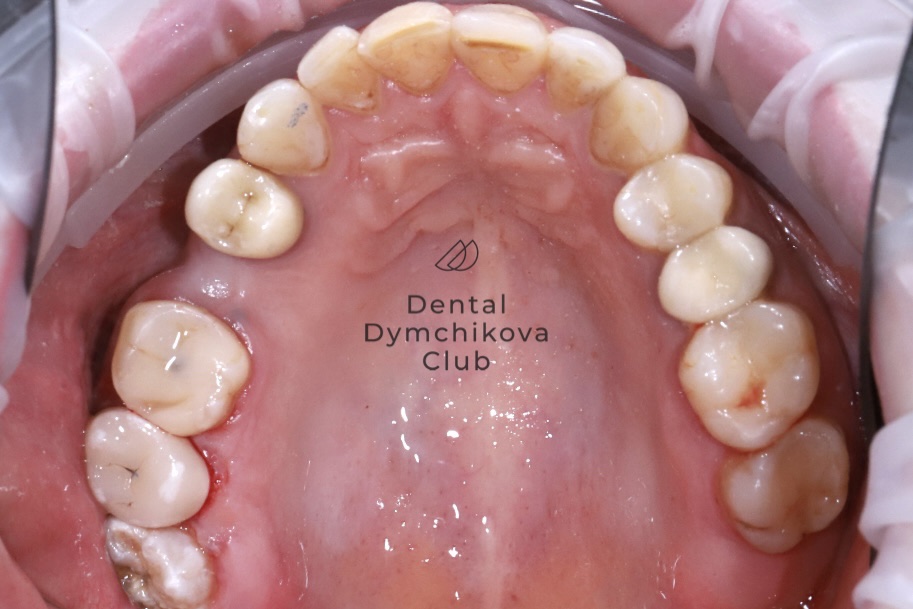

Виниры и коронка

Пациентка, 32 года

Жалобы: на старые пломбы на передних зубах.

Объективно: несостоятельные композитные пломбы, депульпированный зуб 1.1, живые зубы 1.2, 2.1, 2.2, 2.3, наблюдается кариес на живых зубах.

Лечение: установка коронки на зуб 1.1 и лечение кариеса и установка виниров Emax на зубы 1.2, 2.1, 2.2, 2.3.

Срок лечения: 2 недели (2 посещения).

Доктор: Дымчикова Анна Вавиловна